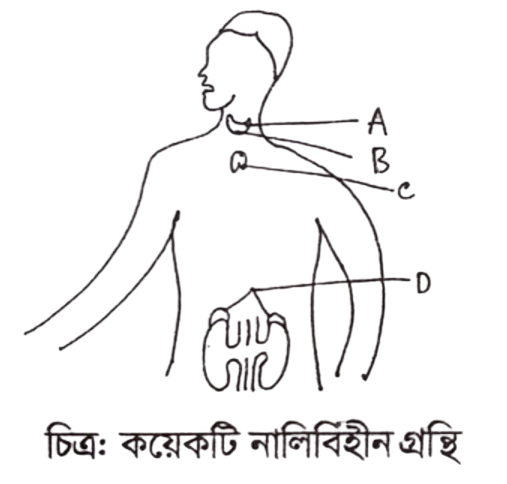

ছবিটি দেখে নিচের প্রশ্নের উত্তর দাও:

ক. গোনাডোট্রপিক

খ. থাইরক্সিন

গ. সোমাটোট্রপিক

ঘ. গ্লুকাগন

উত্তরঃ থাইরক্সিন

ছবিটি দেখে নিচের প্রশ্নের উত্তর দাও:

ক. i ও ii

খ. i ও iii

গ. ii ও iii

ঘ. i, ii ও iii

উত্তরঃ i ও ii